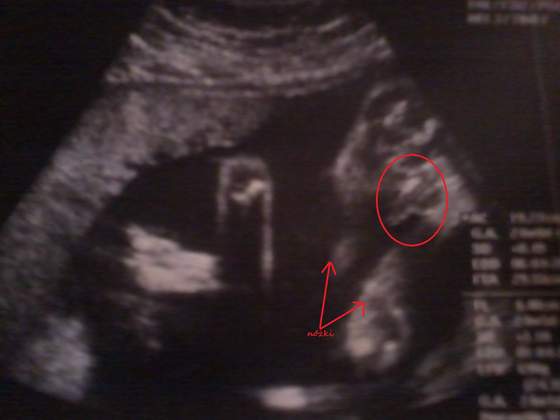

Ja wczoraj także byłam na połówkowym, i umnie wszystko ok, synek rośnie jak szalony, waży juz 600g, (aż nie dowierzałam że az tyle), jest o 2 tyg większy niż termin z OM, a więc termin z USG znowu mi sie przesunął na 10 kwietnia. Wszystkie pomiary wzorowe. widziałam malutkie paluszki, policzyliśmy z gin, i jest po 5 :-)u rączek i nóżek. teraz wizyte mam 10 stycznia i dostałam skierowanie na mocz, morfologie, CRP, ponownie toksoplazmozę i glukozę. I na następnej wizycie robimy 4D.